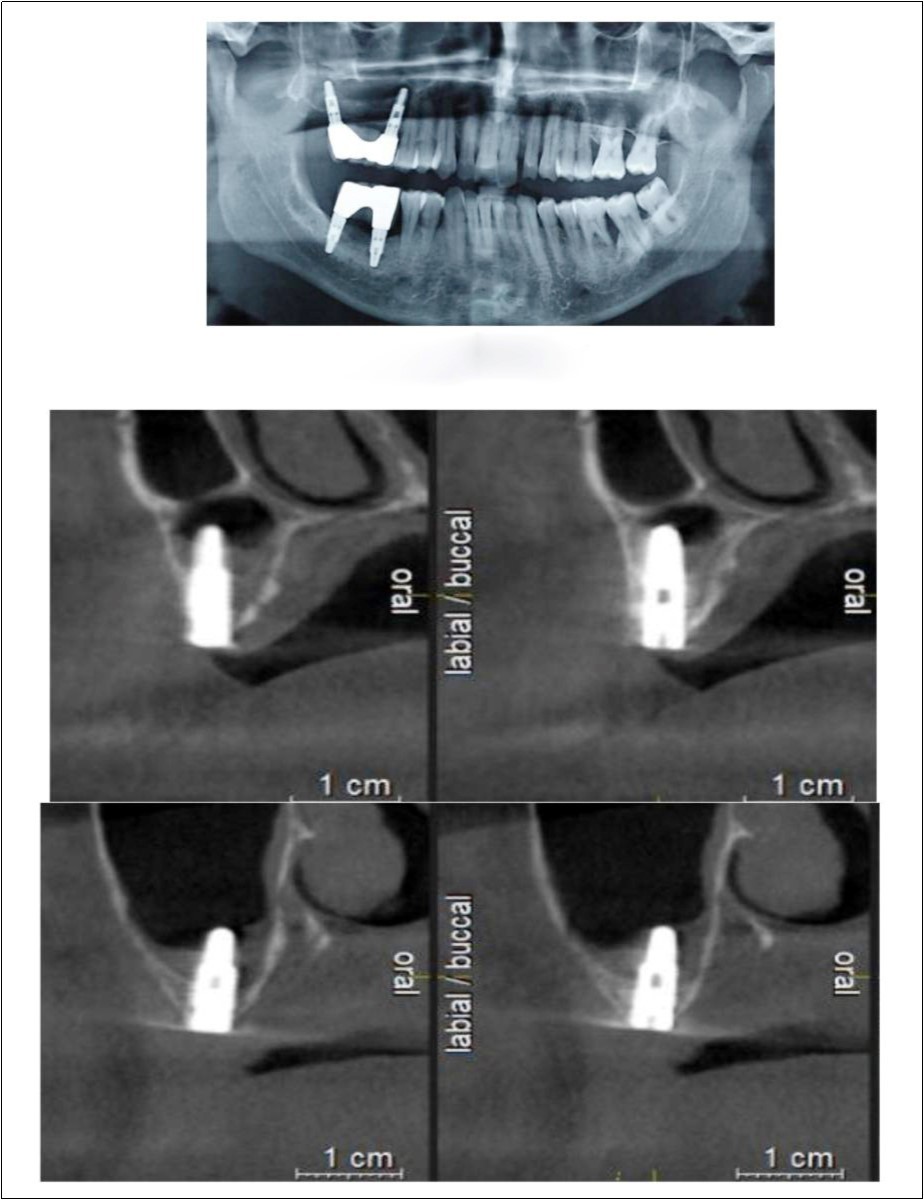

With a pre-operative residual bone height of 0.8 mm in 16 region and 1.5 mm in 17 region, direct sinus augmentation was carried-out in a 40 year old male patient followed by implant placement of 3.75 x 11.5 dimensions as a single step procedure. Lateral window was created and synthetic graft material was dispensed through the lateral osteotomy site to maintain the elevated sinus membrane followed by placement of two dental implants through the crestal approach measuring 3.75 x 11.5 mm under local anesthesia and strict aseptic protocols. At the end of 6 months, a CBCT scan was advised to evaluate the increase in bone height which was 11 mm and 10.8 mm in 16 and 17 region respectively. (Figure 1, Figure 2)

Figure 2.Post-operative Orthopantomograph and cross sections of CBCT showing an increase in residual alveolar bone height